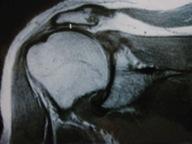

Le bilan à réaliser devant un échec de réparation de la coiffe des rotateurs ne diffère pas beaucoup du bilan standard d’une rupture de la coiffe. L’interrogatoire doit s’attacher à préciser les conditions de réalisation de la première intervention : rechercher une insuffisance diagnostique, une faute technique, un traumatisme précoce ou secondaire, incluant une rééducation agressive. Un bilan d’imagerie comportant une IRM ou un arthroscanner est nécessaire avant toute reprise.

Les conditions locales sont également primordiales pour poser l’indication d’une réparation itérative : état musculaire, tendineux, cartilagineux, osseux et centrage de la tête humérale. Les éléments favorables sont une petite rupture itérative avec un bon état musculaire et tendineux et l’absence d’arthrose.